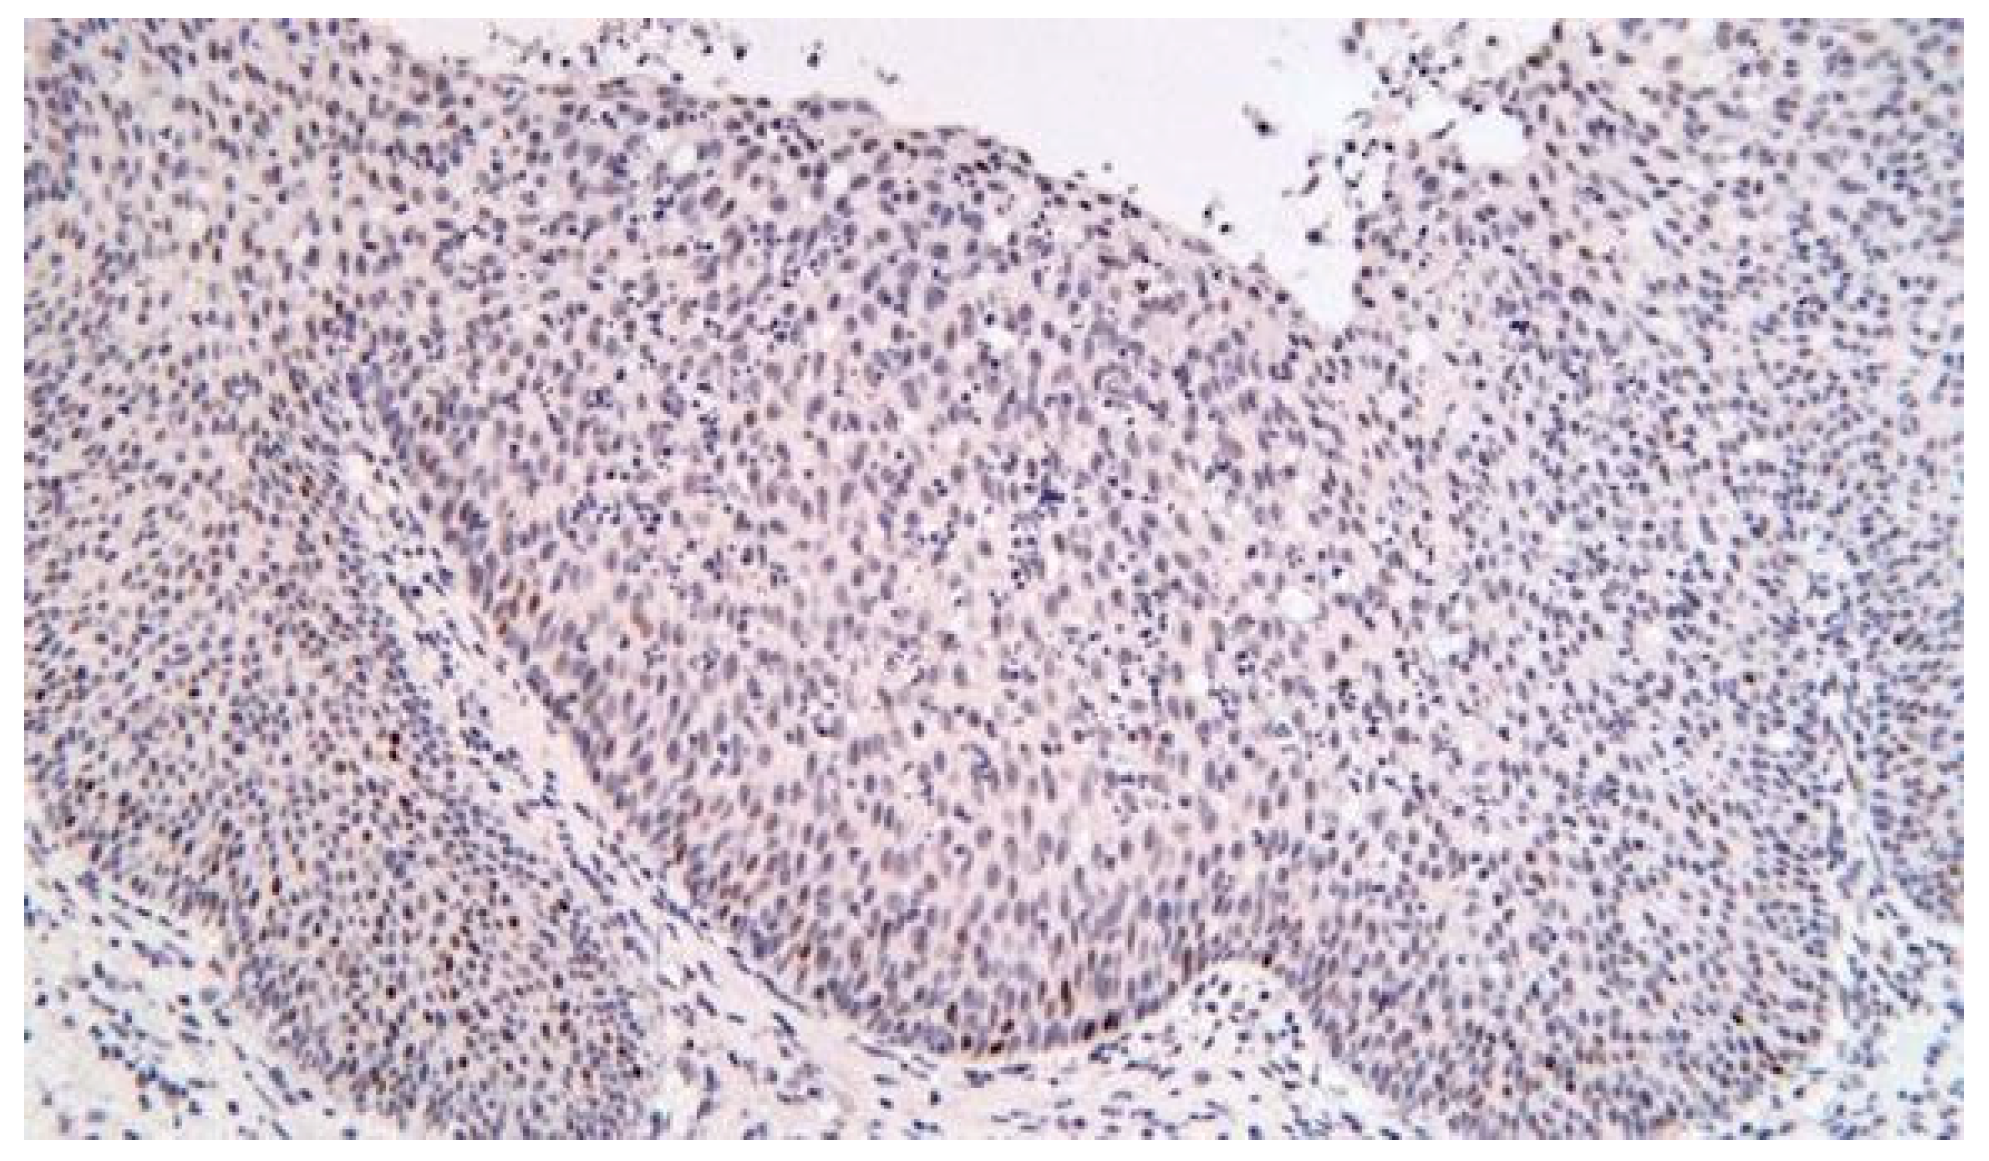

Multiple biopsies ware taken under local anesthesia. The fragments were sent for histopathological (HP) examination (Figure 4).

Biopsy tumor fragments.

HP results reveal: all fragments of respiratory mucosa show at chorionic level, an epithelial papillary pattern proliferation, arranged endophytically. The papillae are composed of stratified squamous epithelium including multiple mucoid cysts and intraepithelial polymorpho-nuclear leukocytes. The chorion is myxoedematous, with moderate diffuse chronic inflammation with multiple eosinophils. Appearance of benign epithelial tumor was represented by Schneiderian papilloma, inverted type.